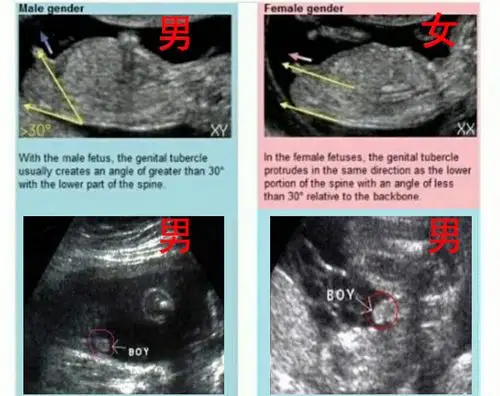

怀孕十二周,生男生女这样看._手机搜狐网

广州妈妈告诉你两张b超图片便可提前知道是男是女